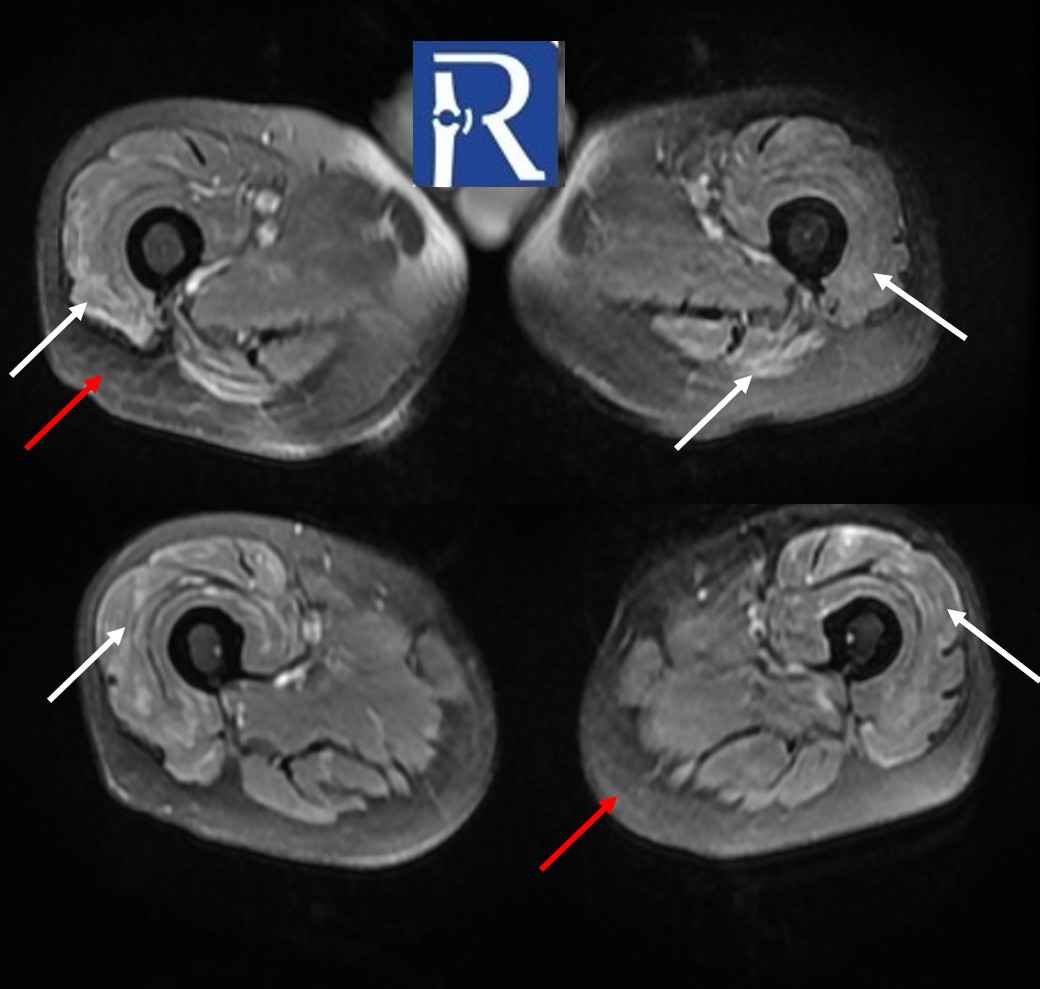

MRI Findings:

MRI of the both thigh reveals bilateral crescent-shaped, geographic lesions in the femoral heads consistent with osteonecrosis (formerly avascular necrosis) (yellow arrows). Additionally, there are bilateral, symmetrical, heterogeneous hyperintense signal changes—resembling edema—predominantly affecting the anterior muscle groups of the thighs (white arrows), indicative of myositis. There is also diffuse loss of subcutaneous fat tissue with focal areas of mildly increased T2 signal (red arrow).